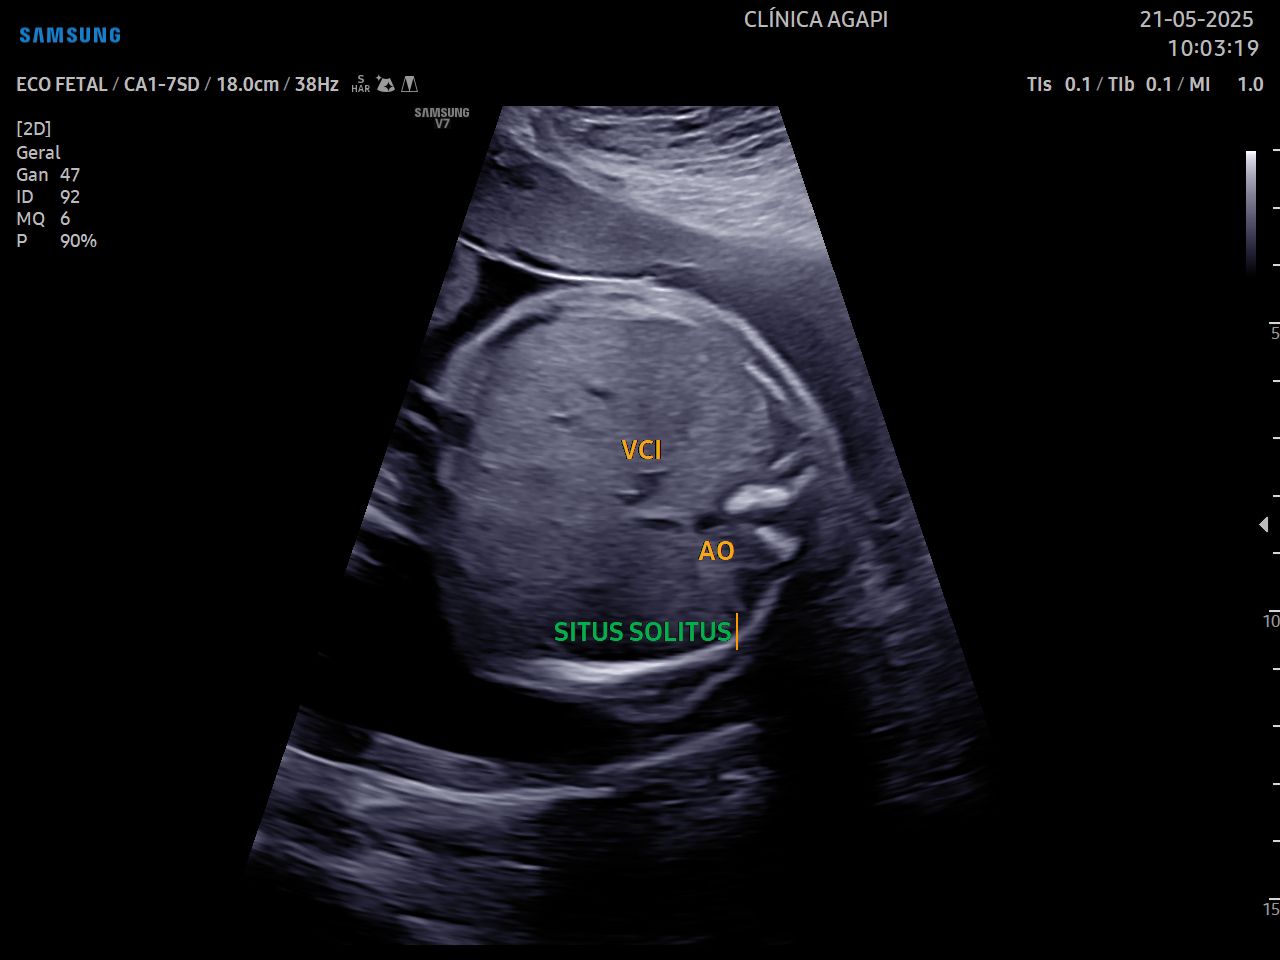

Esse exame é realizado por cardiologista pediátrico e avalia detalhadamente o coração do bebê e suas funções. As cardiopatias congênitas representam a principal causa de mortalidade perinatal por doença congênita e ocorrem com uma prevalência 8 a 12 casos por mil nascidos.

Deve ser realizado preferencialmente entre 26 e 29 semanas de gestação.